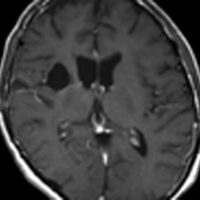

神経下垂体ジャーミノーマと大脳基底核成熟奇形腫

neurophypophyseal germinoma with basal ganglia mature teratoma

12歳の男児が尿崩症で発症しましたが,7ヶ月間診断がつかずに低ナトリウム血症による全身痙攣を生じました。下垂体と右被殻の2箇所に腫瘍があり,AFP 33ng/ml, HCG-beta 1.0mIUと上昇がみられました。神経下垂体の生検術でgerminomaの診断であったために化学療法が開始されました。CPA, VP-16, CDDP, VCRの併用化学療法に,MTXの髄腔内注入が2回でした。なぜこのような乱暴な化学療法を行なったのかは不明です。当然ですが,下垂体のgerminomaは左側のように消失しました。

でも化学療法中に,右大脳基底核にあった腫瘍が増大して,左のMRIのように脳浮腫も悪化しました。この時点で患者さんが転院してきました。腫瘍マーカーは陰転していて,どう見ても奇形腫が化学療法によるparadoxical responseを生じたものでした。ジャーミノーマが消えて奇形腫だけ増大するという現象です。

まず手術で全摘出して,成熟期奇形腫の病理診断を確定しました。それからICE化学療法を2コース加えて,脳脊髄照射 24Gy12分割を行いました。

大脳基底核に胚細胞腫瘍がある場合には全脳照射が基本ですが,なぜ脊髄照射を加えたかということには絶対の根拠はありません。治療前のAFPがやや高く若干の播種性格を有する未熟奇形腫が手術前に消失していたかもしれないという可能性を考えたことと,発症が12歳ですから脊髄照射を24グレイ加えても重篤な遅発性障害が生じないと判断したからです。